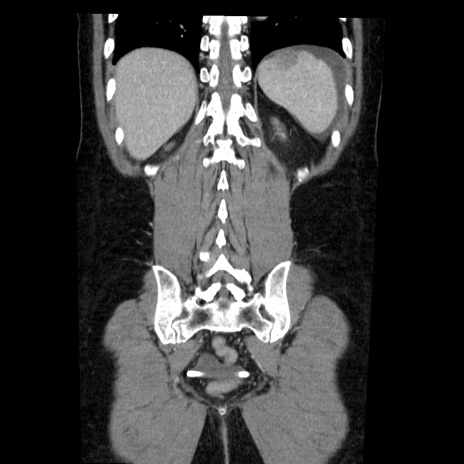

症例6(冠状断像)

【症例】50歳代女性

【主訴】下腹部痛

【現病歴】本日朝より下痢2回あり。 昼食を食べた後、嘔吐3回、下腹部痛認め、症状軽快せず、当院救急搬送。

最終食事:本日昼(生ものなし)。 昨日の夜、刺身を食ぺたとのこと。周囲に同様の症状の者なし。普段、排便は毎日あるとのこと。

【既往歴】卵巣癌術後(8年前に当院で卵巣摘出)

【身体所見】 意識清明、腹部:平坦、腸蠕動音→、やや硬、下腹部自発痛・圧痛あり、反跳痛あり、筋性防御なし。

【データ】WBC 16000、CRP 0.01